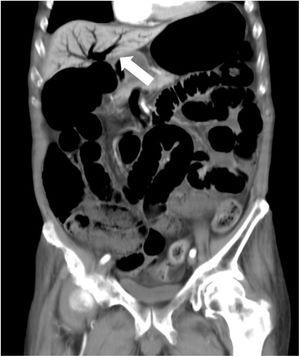

Un hombre de 81 años con historia de diabetes tipo 2 fue admitido en nuestro hospital debido a inflamación abdominal. Seis días antes comenzó a tomar voglibosa. En el examen físico se encontró distensión abdominal, pero no dolor. Una tomografía computarizada abdominal mejorada por contraste reveló un conducto intestinal expandido y enfisema portal (fig. 1). Se suspendió la voglibosa y el paciente fue sometido a laparotomía de urgencia por sospecha de isquemia mesentérica no oclusiva. Sin embargo, no se encontró necrosis intestinal o perforación (fig. 2). Se realizó a continuación descompresión intestinal y se realizó una tomografía computarizada al séptimo día de hospitalización, sin signos de enfisema portal (fig. 3). Se comenzó dieta oral al décimo día. El curso clínico del paciente fue sin incidentes y fue transferido a un hospital de cuidados de largo plazo al día 24. Se sabe que el gas de vena porta es una complicación rara en pacientes que toman inhibidores de alfa glucosidasa (α-GI) y podría ser resultado de neumatosis cistoide intestinal, más que de isquemia intestinal1,2. Puede ser manejado conservadoramente y se debería evitar el tratamiento quirúrgico innecesario.